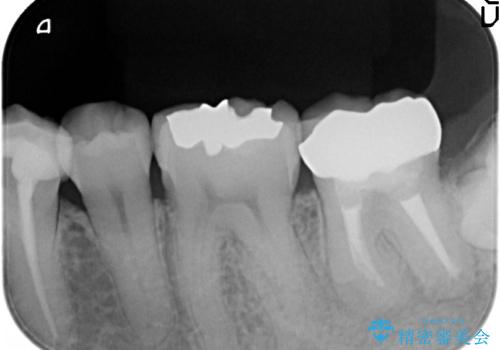

- 左下奥歯でものを咬むと鈍い痛みがあるので診て欲しいといらっしゃった方の症例です。

検査の結果根尖病変(歯根の細菌感染)を認めたため、再根管治療を行いオールセラミッククラウンによる補綴を行いました。